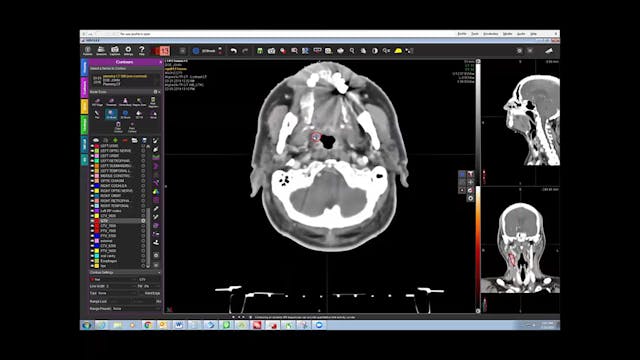

08/06/19 - Dr. Kenneth Hu - Radiation Oncology - Head and Neck US

Chartrounds US - Head and Neck Cancer